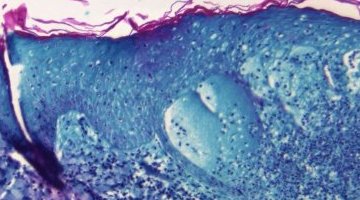

L’agence sanitaire mondiale de l’ONU (OMS) a approuvé le vaccin Mpox de la société ...

L’Organisation mondiale de la santé (OMS) a inscrit le premier test de diagnostic in vitro du ...

La variole du singe a été classée en urgence de santé publique de portée internationale par le ...